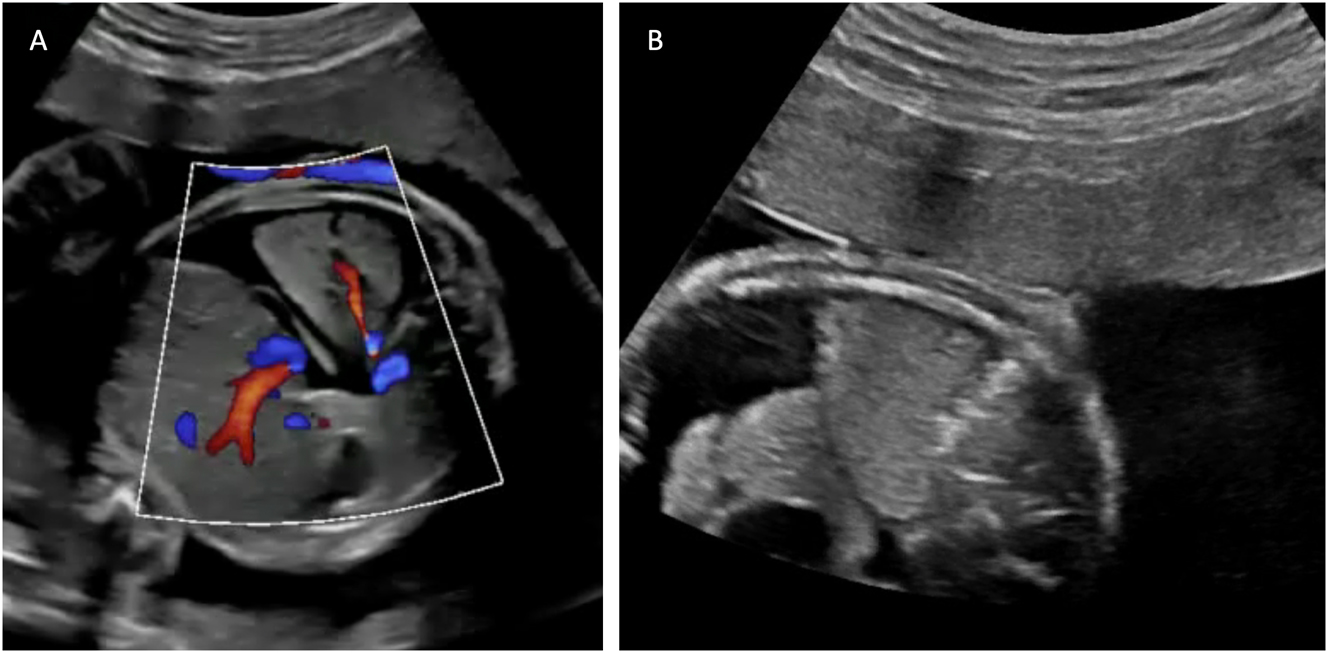

1. aCritically abnormal Doppler measurements is defined as umbilical artery Doppler with absent or reverse flow in end-diastole and/or ductus venosus Doppler with reverse a-wave (Figure 1) or and/or umbilical vein with pulsatile flow.

Figure 1:

Ultrasound findings relevant for TTTS staging. (A) Umbilical artery Doppler with reverse flow in end-diastole and (B) ductus venosus Doppler with reverse a-wave. (C) Hydropic fetus with ascites and skin oedema.

The Twin Reversed Arterial Perfusion Sequence (TRAP) is another complication occurring in monochorionic twins, with an incidence of 1 in 35.000 pregnancies [57]. This is the most extreme form of interfetal transfusion. Through an AA anastomosis of the monochorionic placenta, one twin (pumping twin) pumps blood retrograde via the umbilical cord into the arterial system of the other twin (parasitic co-twin). The latter develops hydrops fetalis at an early stage, the heart regresses and pronounced malformations of the upper half of the body (acardius acranius) are the result. The sonographically unremarkable pumping twin supplies the parasitic co-twin with blood, and this severe circulatory strain often leads to hyperdynamic heart failure, hydrops fetalis, and intrauterine death. With conservative management, approximately half of pumping twins survive [57]. The TRAP sequence can be diagnosed by experienced prenatal diagnosticians as early as the first trimester of pregnancy (Figure 7). After diagnosis at 12 weeks of pregnancy, 33 % of pumping twins in utero have died spontaneously and unpredictably by 16 weeks of pregnancy [58]. Spontaneous cessation of retrograde perfusion of the acardius occurs in approximately 20 % of cases [58]. In untreated cohorts, mortality rates exceeding 50 % have been reported for the pump twin, primarily due to progressive high-output cardiac failure and resulting preterm delivery [57], 59].

Figure 7:

Parasitic twin (acardius acranius) with absent heart and head, and retrograde umbilical artery perfusion.